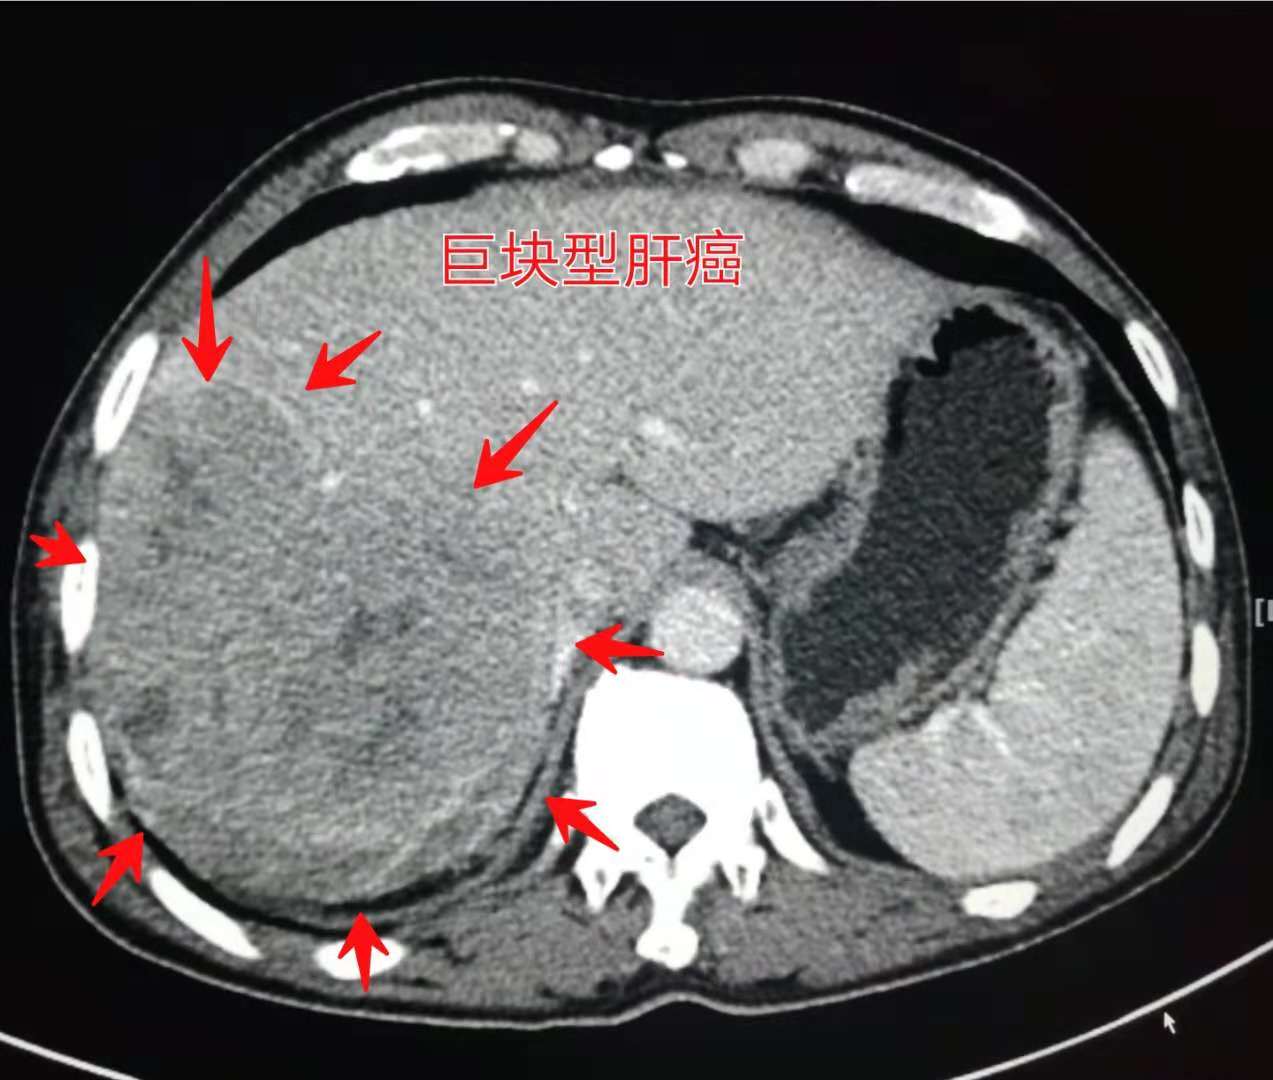

比如这一位病人,巨块型肝癌,确诊的时候肿瘤就比拳头还要大了。

这种程度如果不治疗会快速进展,一般寿命不超过三个月,短的甚至只有二十几天。曾经肝癌被称作“癌中之王”,就是这个原因。

当然这个病人没有放弃治疗,选用介入栓塞配合消融治疗,三年半后还活着:

这个病人比较幸运,对治疗有效!并且三年多的时间没有发生转移和复发。